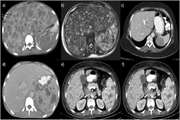

Diagnostic performance of different imaging modalities for splenic malignancies: A comparative meta analysis 1403/12/27 - 09:46